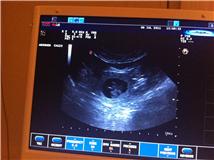

Bilder fra Ultralyd 6/7-2011:

Her ser du et.

Dette er en noe usikker metode for å vite hvor mange valper det er, men vet i hvertfall at hun er drektig. Vi kunne telle fem valper, men det er veldig usikkert. Det kan være flere eller færre. Tiden vil vise.